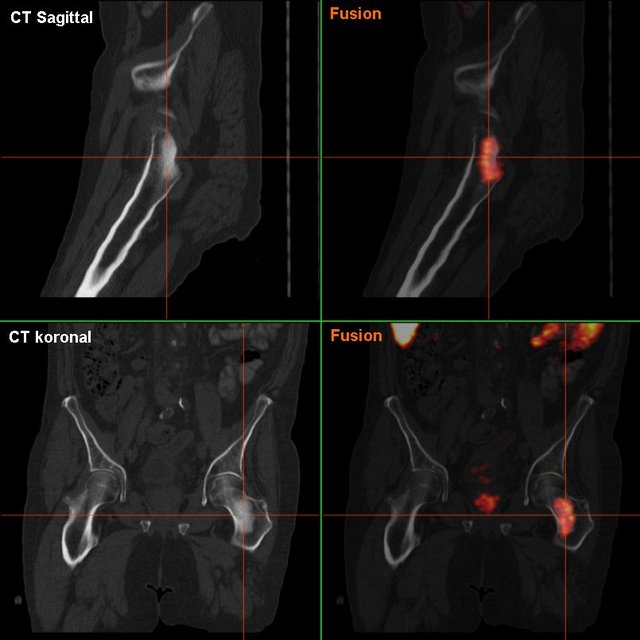

Osteoplastische Knochenmetastase im Hüftgelenk in der F-18-Cholin PET-CT; Knochenmetastasen des Prostata-Karzinoms sind meist osteoplastisch, d. h. knochenaufbauend © wikipedia.org/Hg6996, CC BY-SA 3.0